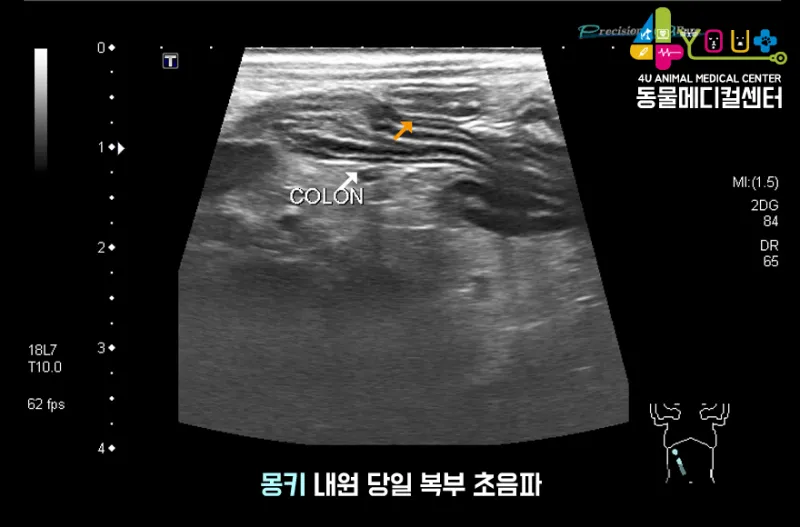

감염성 복막염은 주로 다른 장기의 염증이 확산되면서 발생해요. 예를 들어, 심한 췌장염이나 담낭염이 주변 복막으로 번지는 경우죠. 이런 경우엔 원발 질환 치료와 함께 복막염 관리를 동시에 해야 해서 치료가 더 복잡해집니다.